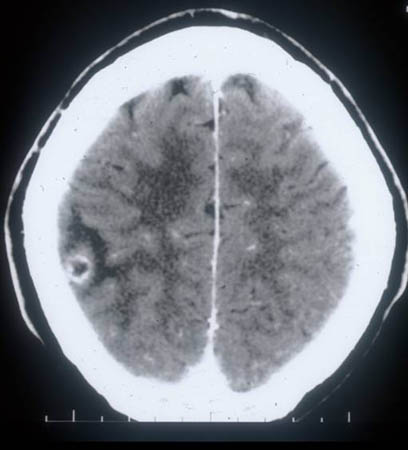

TC cranioencefálica

Exame

A neuroimagem é a base do diagnóstico para a neurocisticercose.[33][40] A RNM é superior à TC na identificação de cistos extraparenquimatosos e lesões da fossa posterior, mas a TC é melhor na visualização dos cistos calcificados.[39] Idealmente, ambos os testes devem ser considerados.

Achados específicos dependem da localização dos cistos:[33]

Parenquimatosa (calcificada não viável): calcificações nodulares <20 mm de diâmetro (geralmente 1-5 mm) com ou sem edema circundante e/ou captação de contraste.

Parenquimatosa (viável): lesão vesicular com evidência de captação de contraste e/ou edema circundante; o escólex costuma ser visível.

Parenquimatosa - realce único e pequeno: lesão com realce cístico ou nodular <2 cm.

Extraparenquimatosa (intraventricular): cisticercos nos ventrículos; hidrocefalia obstrutiva ou loculada com dilatação desproporcional dos ventrículos.

Extraparenquimatosa (subaracnoide): cisticercos em fissura silviana, cisternas basilares ou espaços inter-hemisféricos.

Extraparenquimatosa (espinhal): cisticercos no espaço subaracnoide espinhal com ou sem inflamação/aracnoidite espinhal difusa; cisticercos intramedulares na medula espinhal.[Figure caption and citation for the preceding image starts]: Estádio coloidal - neurocisticercose: tomografia computadorizada (TC) mostrando lesão cística com realce em anel no lobo temporal e edema perilesionalDo acervo da Dra. Christina Coyle e do Dr. Maheen Saeed; usado com permissão [Citation ends].

Resultado

calcificações do cérebro são comuns; achados específicos dependem da localização dos cistos